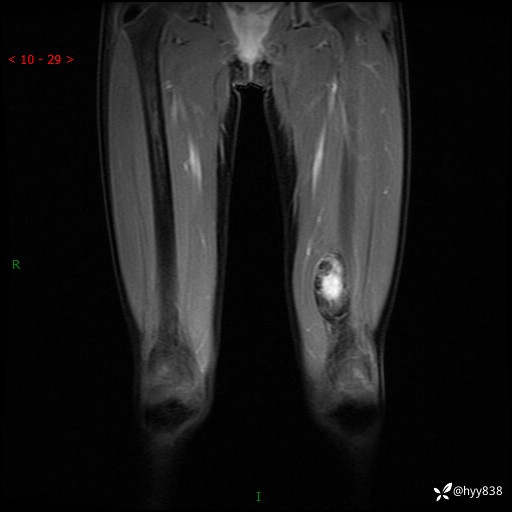

左大腿MRI平扫+增强